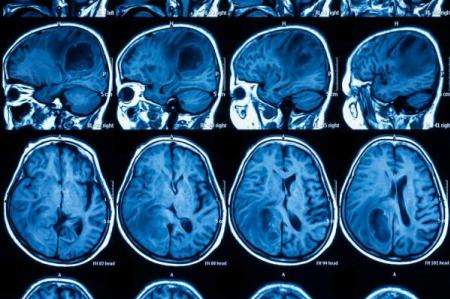

گلیوبلاستما (یک نوع سرطان مغز)، تومورهای تهاجمی و سریع الرشد هستند که آستروسیت ها یعنی سلول هایی را تشکیل می دهند که بافت حمایت کننده مغز را می سازند.

طبق اعلام انجمن تومور مغز آمریکا، آستروسیت ها به سرعت تکثیر می شوند و توسط شبکه بزرگی از رگ های خونی حمایت می شوند، به همین دلیل درمان این سرطان نسبتا نادر بسیار دشوار است.